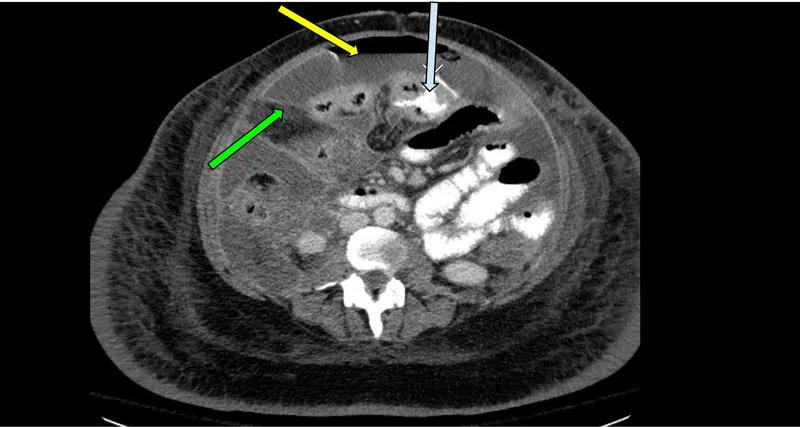

- CT abdomen/pelvis with contrast: >95% sensitivity, shows site and cause

- Stable patient: Erect CXR → CT abdomen/pelvis with IV contrast

⚠️ Warning: Up to 30% of perforations have no free gas on CXR - CT is gold standard if clinical suspicion persists

✓ Imaging hierarchy: Erect CXR (70-80% sensitive) → CT with contrast (>95% sensitive, shows site/cause)